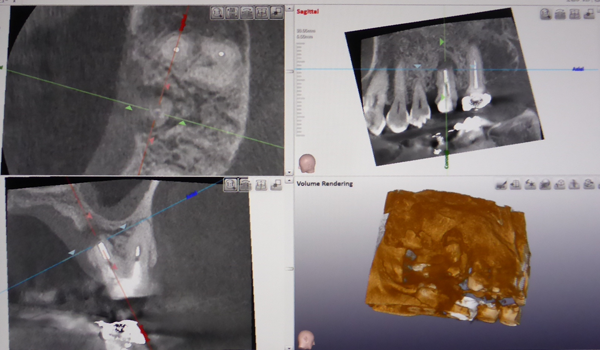

使用例

抜歯

下の顎には太い神経と血管が走っており、特に下の親知らずの抜歯の時、傷つけないように注意が必要になります。

従来のレントゲンではこの太い神経・血管が鮮明に映らないことが多く、安全に抜歯するためにCTを撮影します。 また埋伏過剰歯を抜く場合にも使用します。

インプラント治療

しかし歯周病などの原因で骨が少ないケースがあります。骨の量を確認するためにCTは必要となります。

下の奥歯にインプラント処置をする場合、下歯槽神経などの重要な神経を傷つけないために下歯槽管の位置を確認するために使用します。